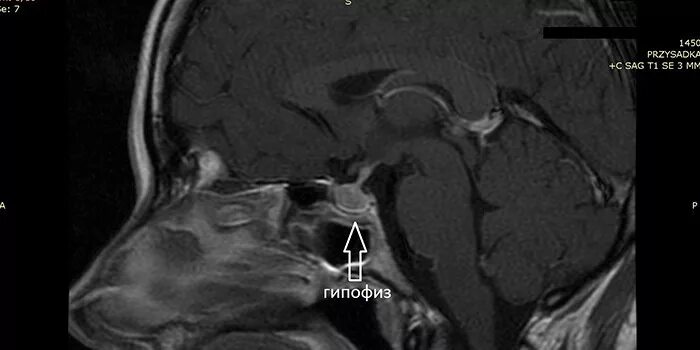

Макроаденома гипофиза